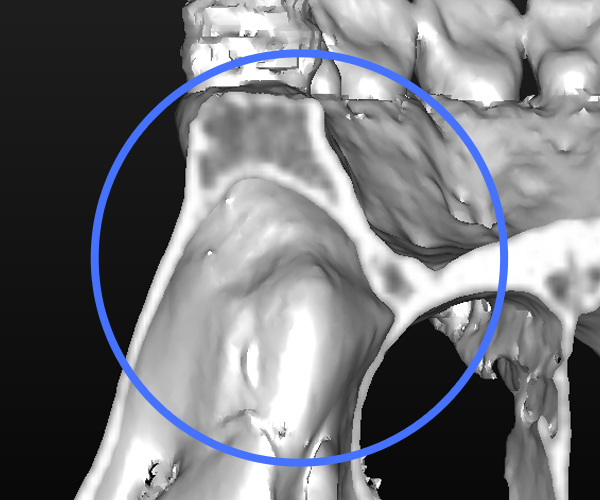

After

約7ヶ月間の根管洗浄・殺菌により、病巣も消失し、副鼻腔の肥厚もなくなり、歯槽骨の再生が得られた